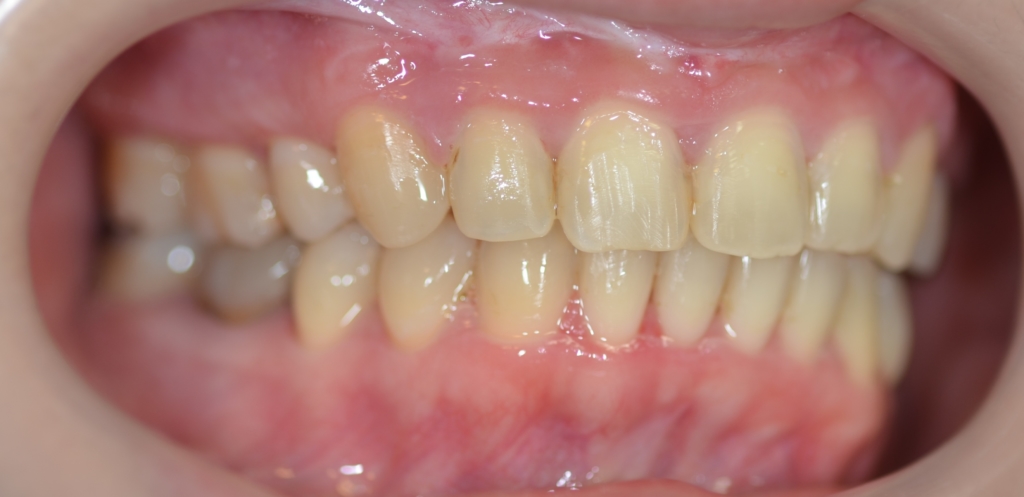

【Before】

【診断】

#1.上顎前突

#2.ガミースマイル(重度の過蓋咬合を伴う)

と診断しました。

補足:口腔前庭縮小術の既往あり(美容外科にて)